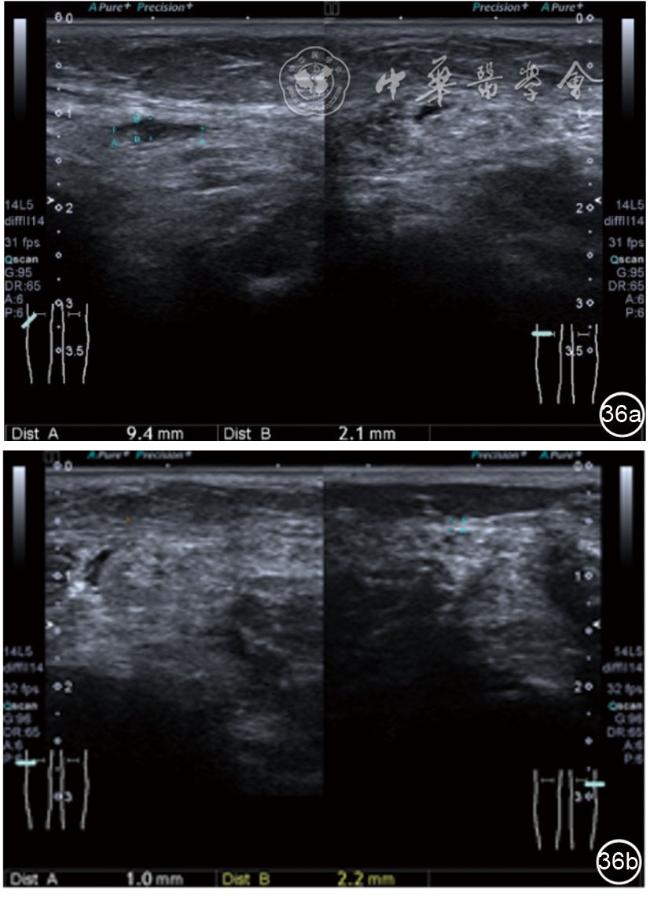

(五)超声影像学表现

患者采取侧卧位,患肢在上,屈膝20°。应用10~18 MHz高频线阵探头,扫查深度1~3 mm。长轴和短轴结合双侧对比扫查。超声影像学所见:短轴可见卡压腓总神经近端增粗,面积增大;长轴可见腓总神经卡压处变细,其近侧肿胀、回声减低,而在卡压远侧则表现正常(图35);一些受压严重者可以出现神经周围积液,卡压神经部位的筋膜增厚(图36);受压神经内血流增加对临床诊断意义更大(图37);探头在病变神经处加压常可引起神经刺激症状。腓总神经支配的肌肉有失神经支配改变,表现为肌肉回声增高和肌肉萎缩(图38)。

图36 超声图像示腓总神经周围积液,卡压神经部位的筋膜增厚